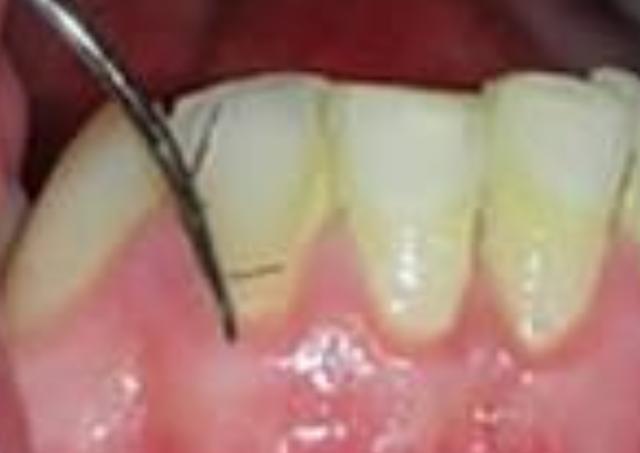

之前文章里写到的巴氏刷牙法,有小伙伴私信问到,就发在这里啦!

巴氏刷牙法。在学习正确的刷牙方式的同时,大多数人可以使用垂直刷牙法或短横向振动法。必要时使用牙签和牙线清洁难以触及的部位。